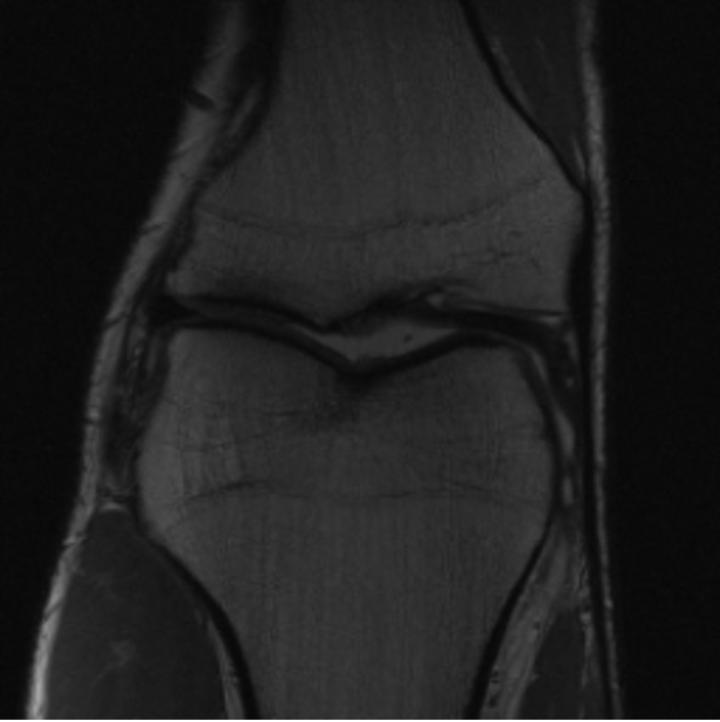

One way to test the generalization capability of the trained X-Diffusion is to test it on a completely different domain from an MRI dataset not seen during training. We report the single-slice results on the test set of knees from NYU fastMRI [33, 80], using the X-Diffusion trained on the BRATS brain MRIs. The test PSNR result is 34.17 and an example is shown in Figure 8. It shows how successfully X-Diffusion can generate knee MRIs (out-of-domain) despite being trained on brains.

Small Knee MRIs clinical study. To qualitatively assess how realistic our generated knee out-of-domain 3D volumes were (produced from a single slice), we gave 20 generated examples alongside their real MRI counterparts to an expert orthopedic surgeon J. F.. He was then asked to identify the real example from a set of 20 MRI pairs. The surgeon correctly identified the real MRI in only 10 out of 20 pairs, could not decide in 3 pairs, and misidentified the generated MRI as real in the remaining 7 pairs. This further validates the generated out-of-domain MRIs.